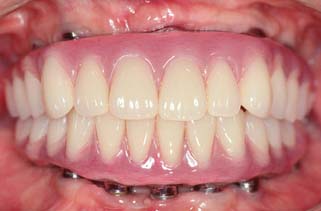

Today the continued high rate of success achieved with osseous integrated dental implants allows a greater number of patients to enjoy the benefits of fixed rather than removable dental prostheses.1-3 The main indications for implant-supported restorations in the partially edentulous patient are the free-end distal extension, in which no posterior abutment is available (Fig. 13-1), and the long edentulous span. In both these situations, the conventional dental treatment plan would include a partial removable dental prosthesis. However, with the advent of dental implants, the patient can benefit from fixed restorations. In addition, in the short edentulous span, the single dental implant is a popular option (Fig. 13-2).

Fig. 13-1 Implant-supported fixed prosthesis. Four dental implants (A) supporting a fixed dental prosthesis (B).